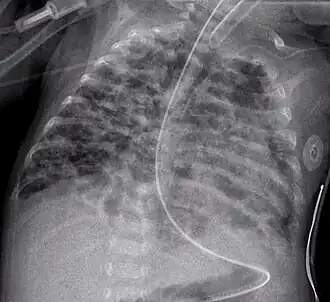

Una radiografía torácica mostrando displasia broncopulmonar. -

Placa portátil (o sea, anteroposterior) mostrando tubo endotraqueal y tubo nasogástrico, ambos en correcta posición.